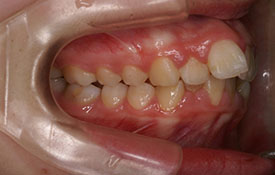

上顎前突|ブラケットを用いた治療

CASE 1

CASE 2